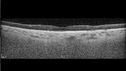

Polypiodal Choroidal Vasculopathy - Temporal Macula - Left eye

82 year old man with asymptomatic PCV in the left eye. Vision 20/50 OD, 20/32 OS did well with Lucentis